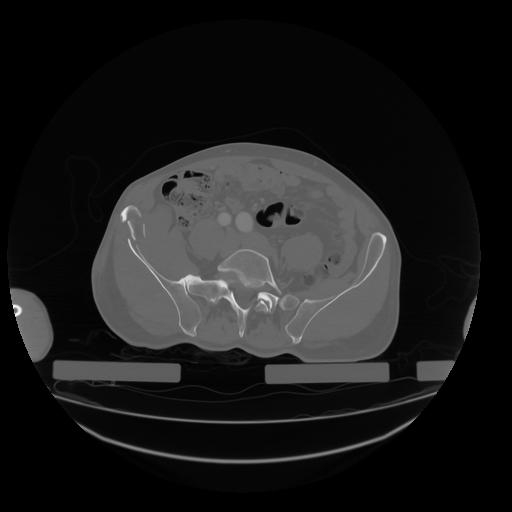

28 CUERPO,CE,Vol,2.0,CUERPO,,